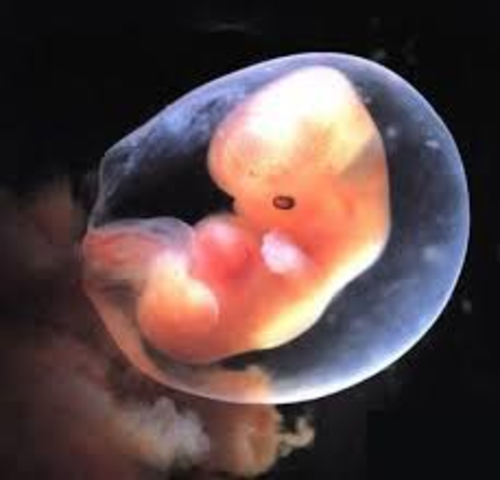

• Week 5

Week 5

The embryo now starts the process of shaping into a human. The placenta is developing and amniotic fluid begins to build up whcih will surround the fetus. The embryo is about 2-5mm.